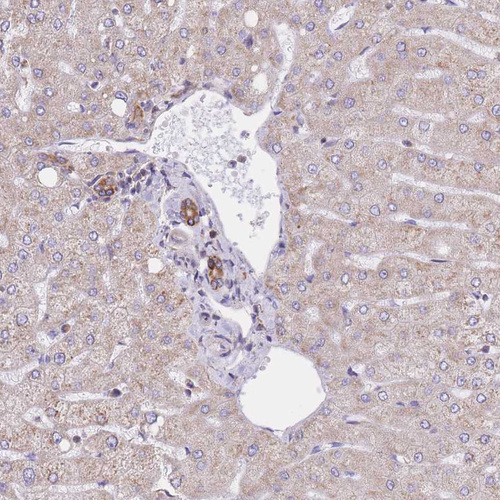

Immunohistochemical staining of human liver shows moderate cytoplasmic and membranous positivity in bile duct cells.